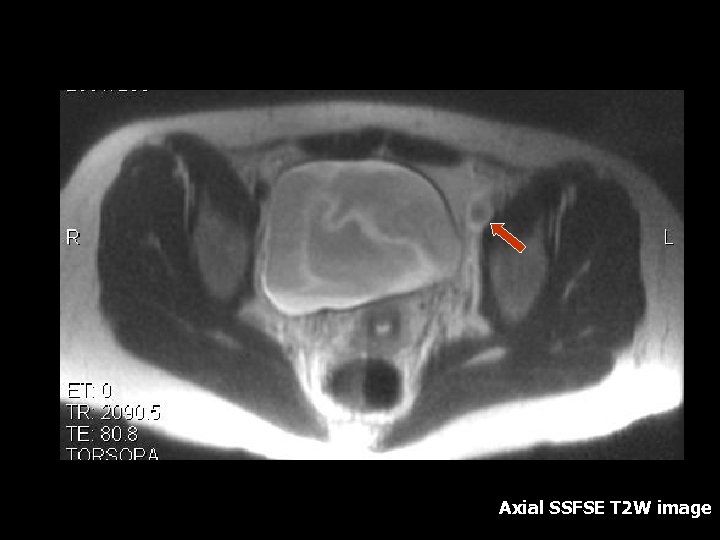

Ovarian Torsion • Fifth most common gynecologic diagnosis(8). • Symptoms – Abdominal pain, nausea and vomiting(8). • Early diagnosis can salvage ovarian function(10%)(8). • Torsion produces circulatory stasis, initially venous, then progresses to arterial(9). • Predisposing factors include ipsilateral adnexal mass, usually benign(9). • Teratoma is the most common benign neoplasm(9).

Torsion • • • MRI findings: Tube thickening(84%) Ovarian cystic mass(76%) Ascites(64%) Deviation of the uterus(36%) Less Common: Hemorrhage and hemoperitoneum

Axial SSFSE T 2 W image